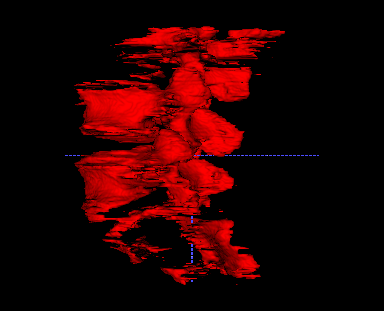

To further improve the segmentation performance, we introduce the 3D segmentation network as in Fig. 3. Our 3D model increases the Dice score from 0.819 to 0.926 and reduces the average ASD by 44% (from 1.47mm to 0.82mm). As shown in Fig. 7, the typical inter-slice discontinuous problem happening in 2D segmentation is fixed with our 3D model, which also runs over 100 times faster than slice-by slice 2D segmentation as measured on a PC with an Intel Xeon E5-2678 and a Nvidia GeForce GTX 2080 Ti.

2D Net

3D Net